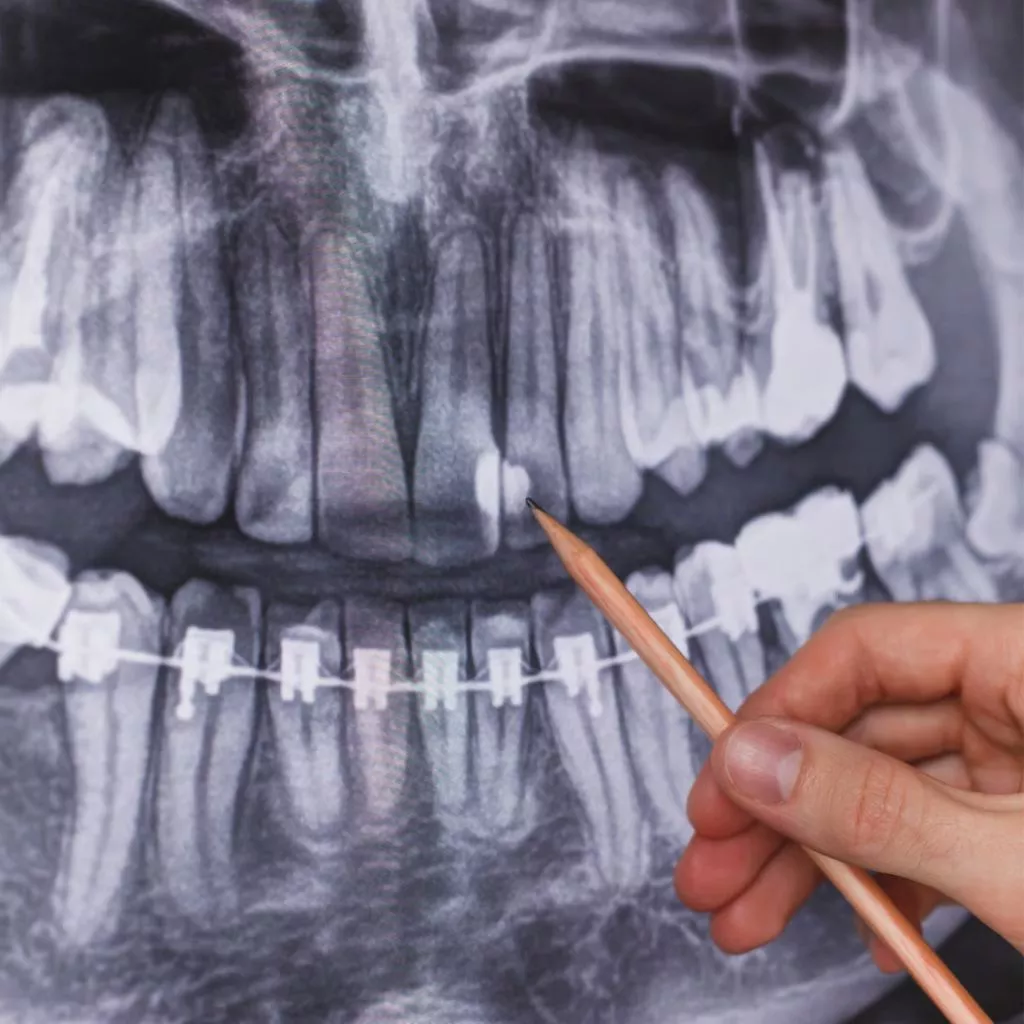

En Channel Islands Family Dental, utilizamos imágenes dentales intraorales de última generación para ofrecer evaluaciones precisas y detalladas de su salud oral. Esta avanzada tecnología nos permite capturar imágenes de alta calidad de sus dientes y encías, lo que permite planes de tratamiento precisos y personalizados. Visite nuestras ubicaciones en Oxnard, Santa Paula, Ventura, Newbury Park y Port Hueneme para descubrir cómo la imagen dental intraoral puede mejorar su experiencia de cuidado dental.